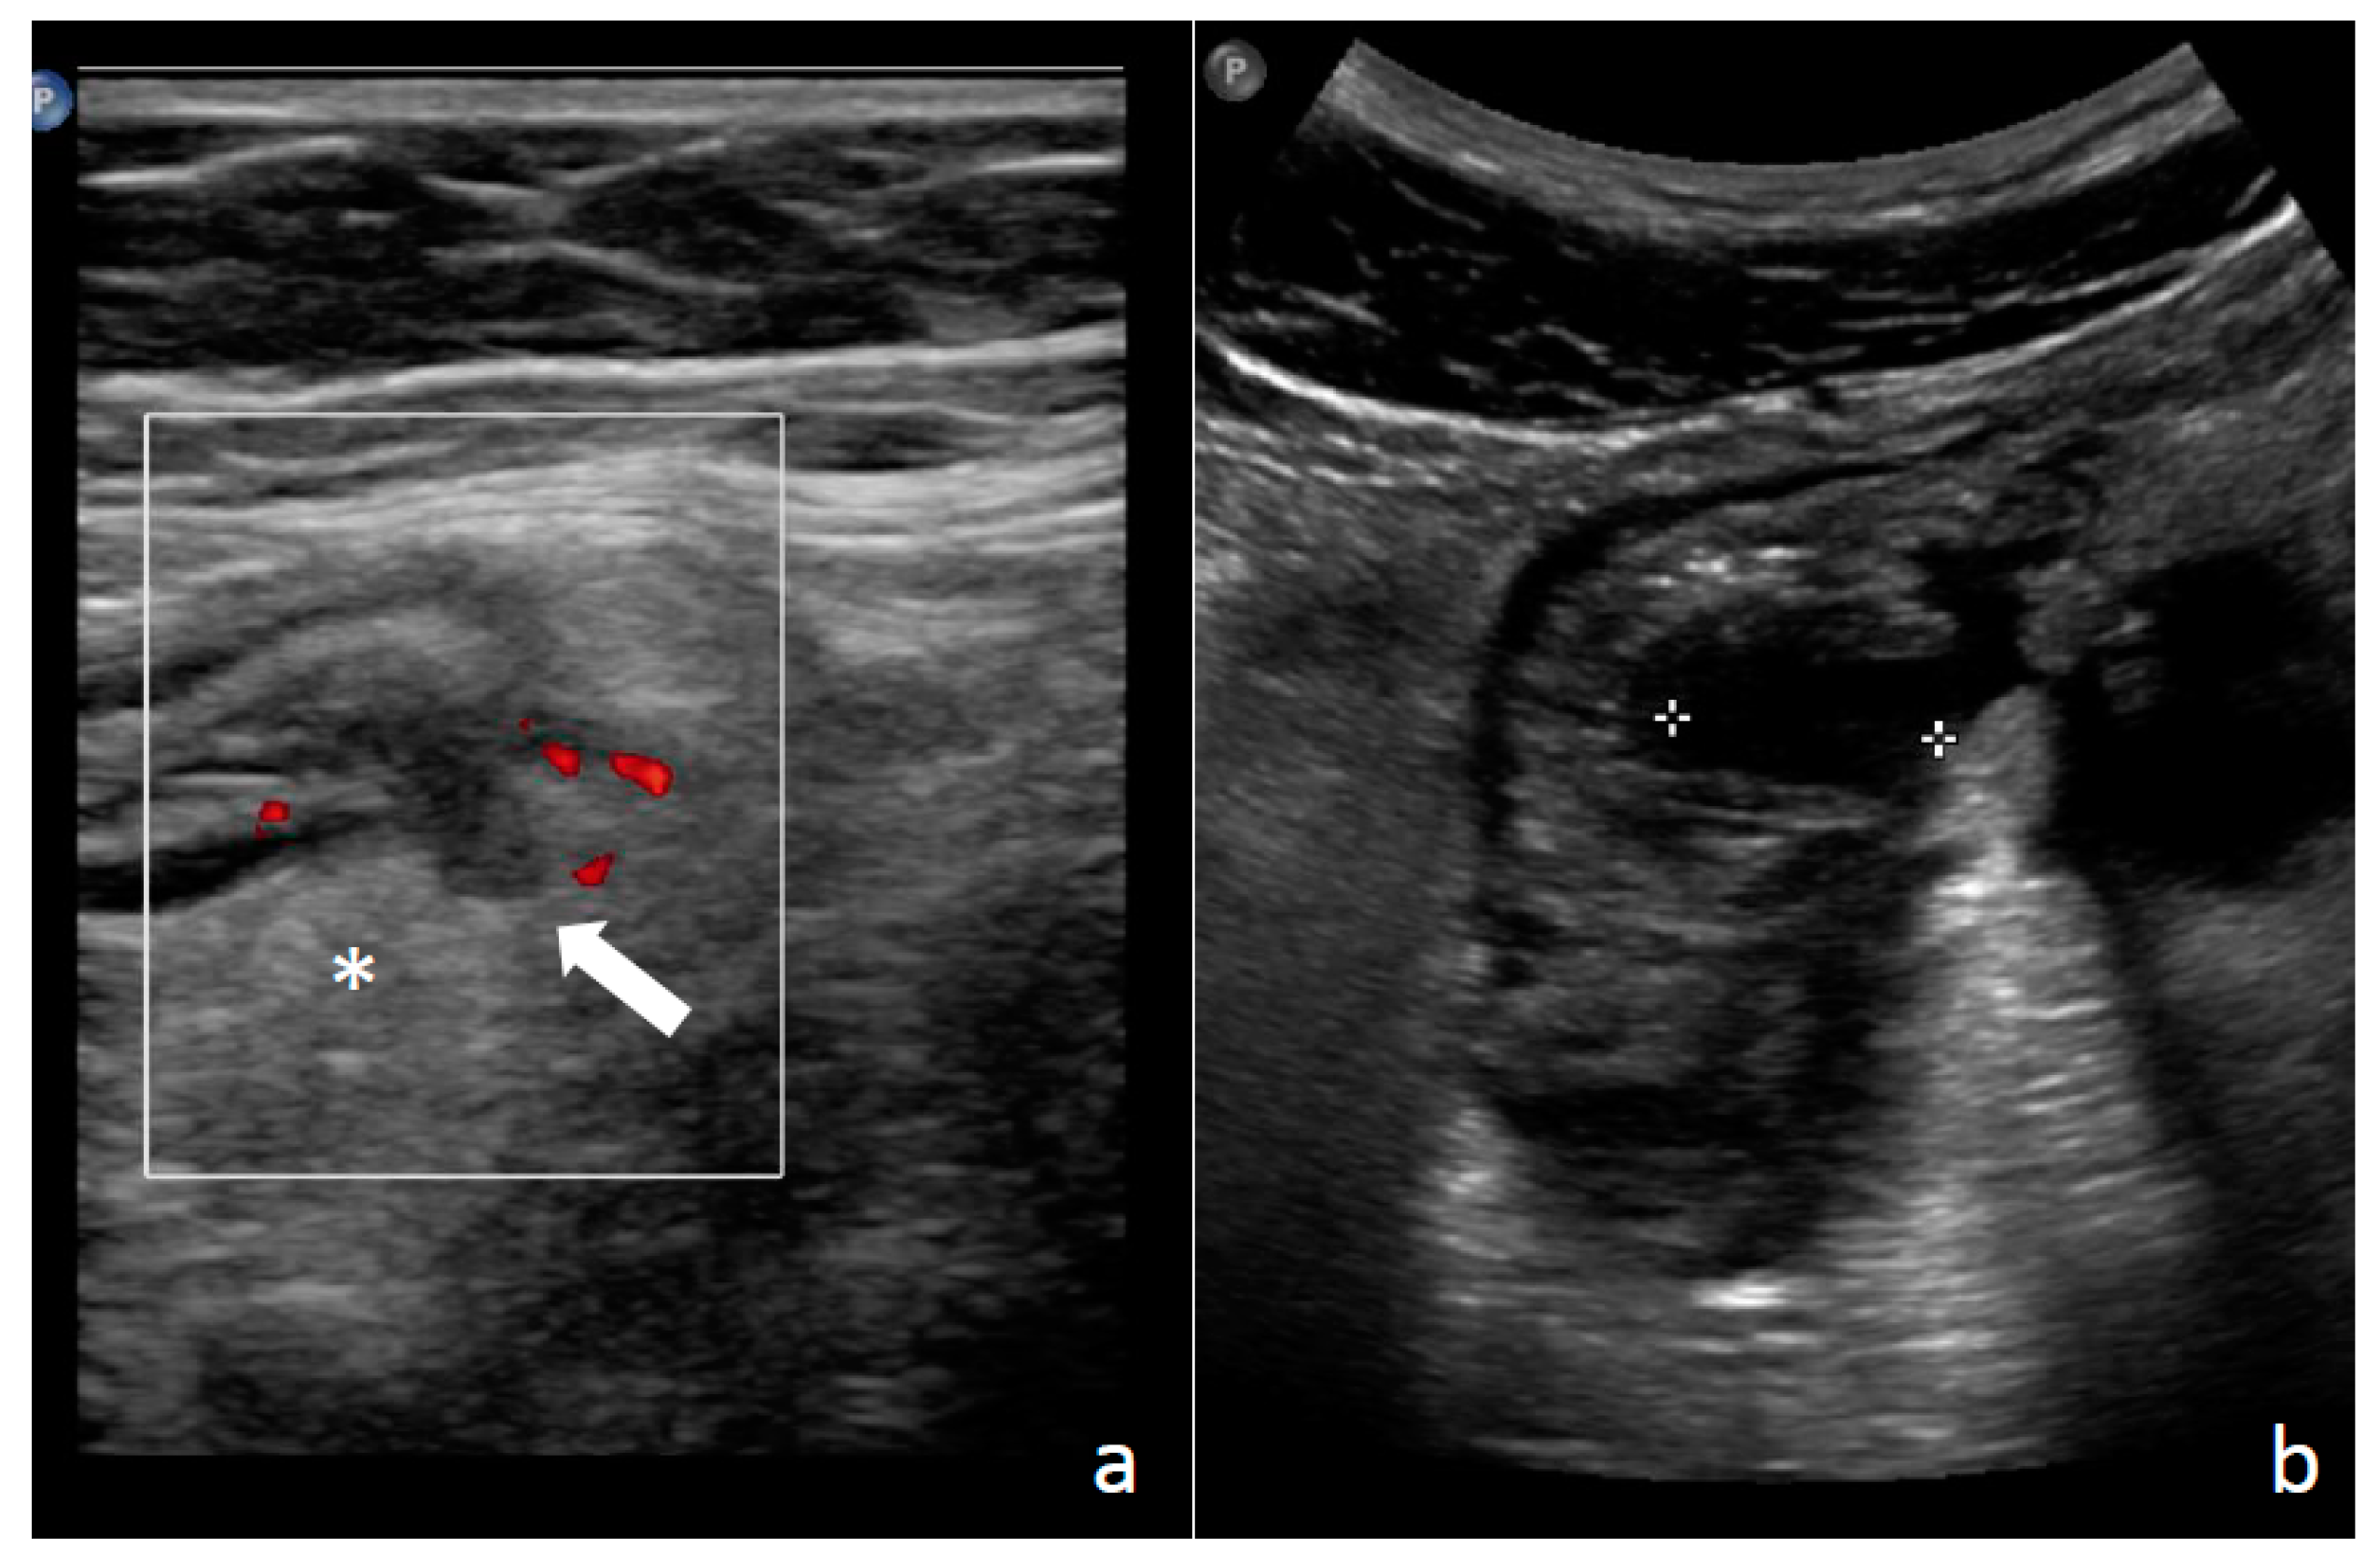

1.3. Diagnosis: Clinical Findings, Laboratory, Imaging, and Endoscopy